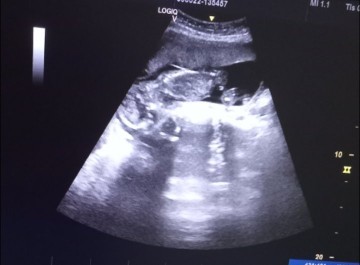

ตอนนี้น้องกลับหัวแล้ว น้ำหนักอยู่ที่ 1430 กรัม 29+2 ค่ะ